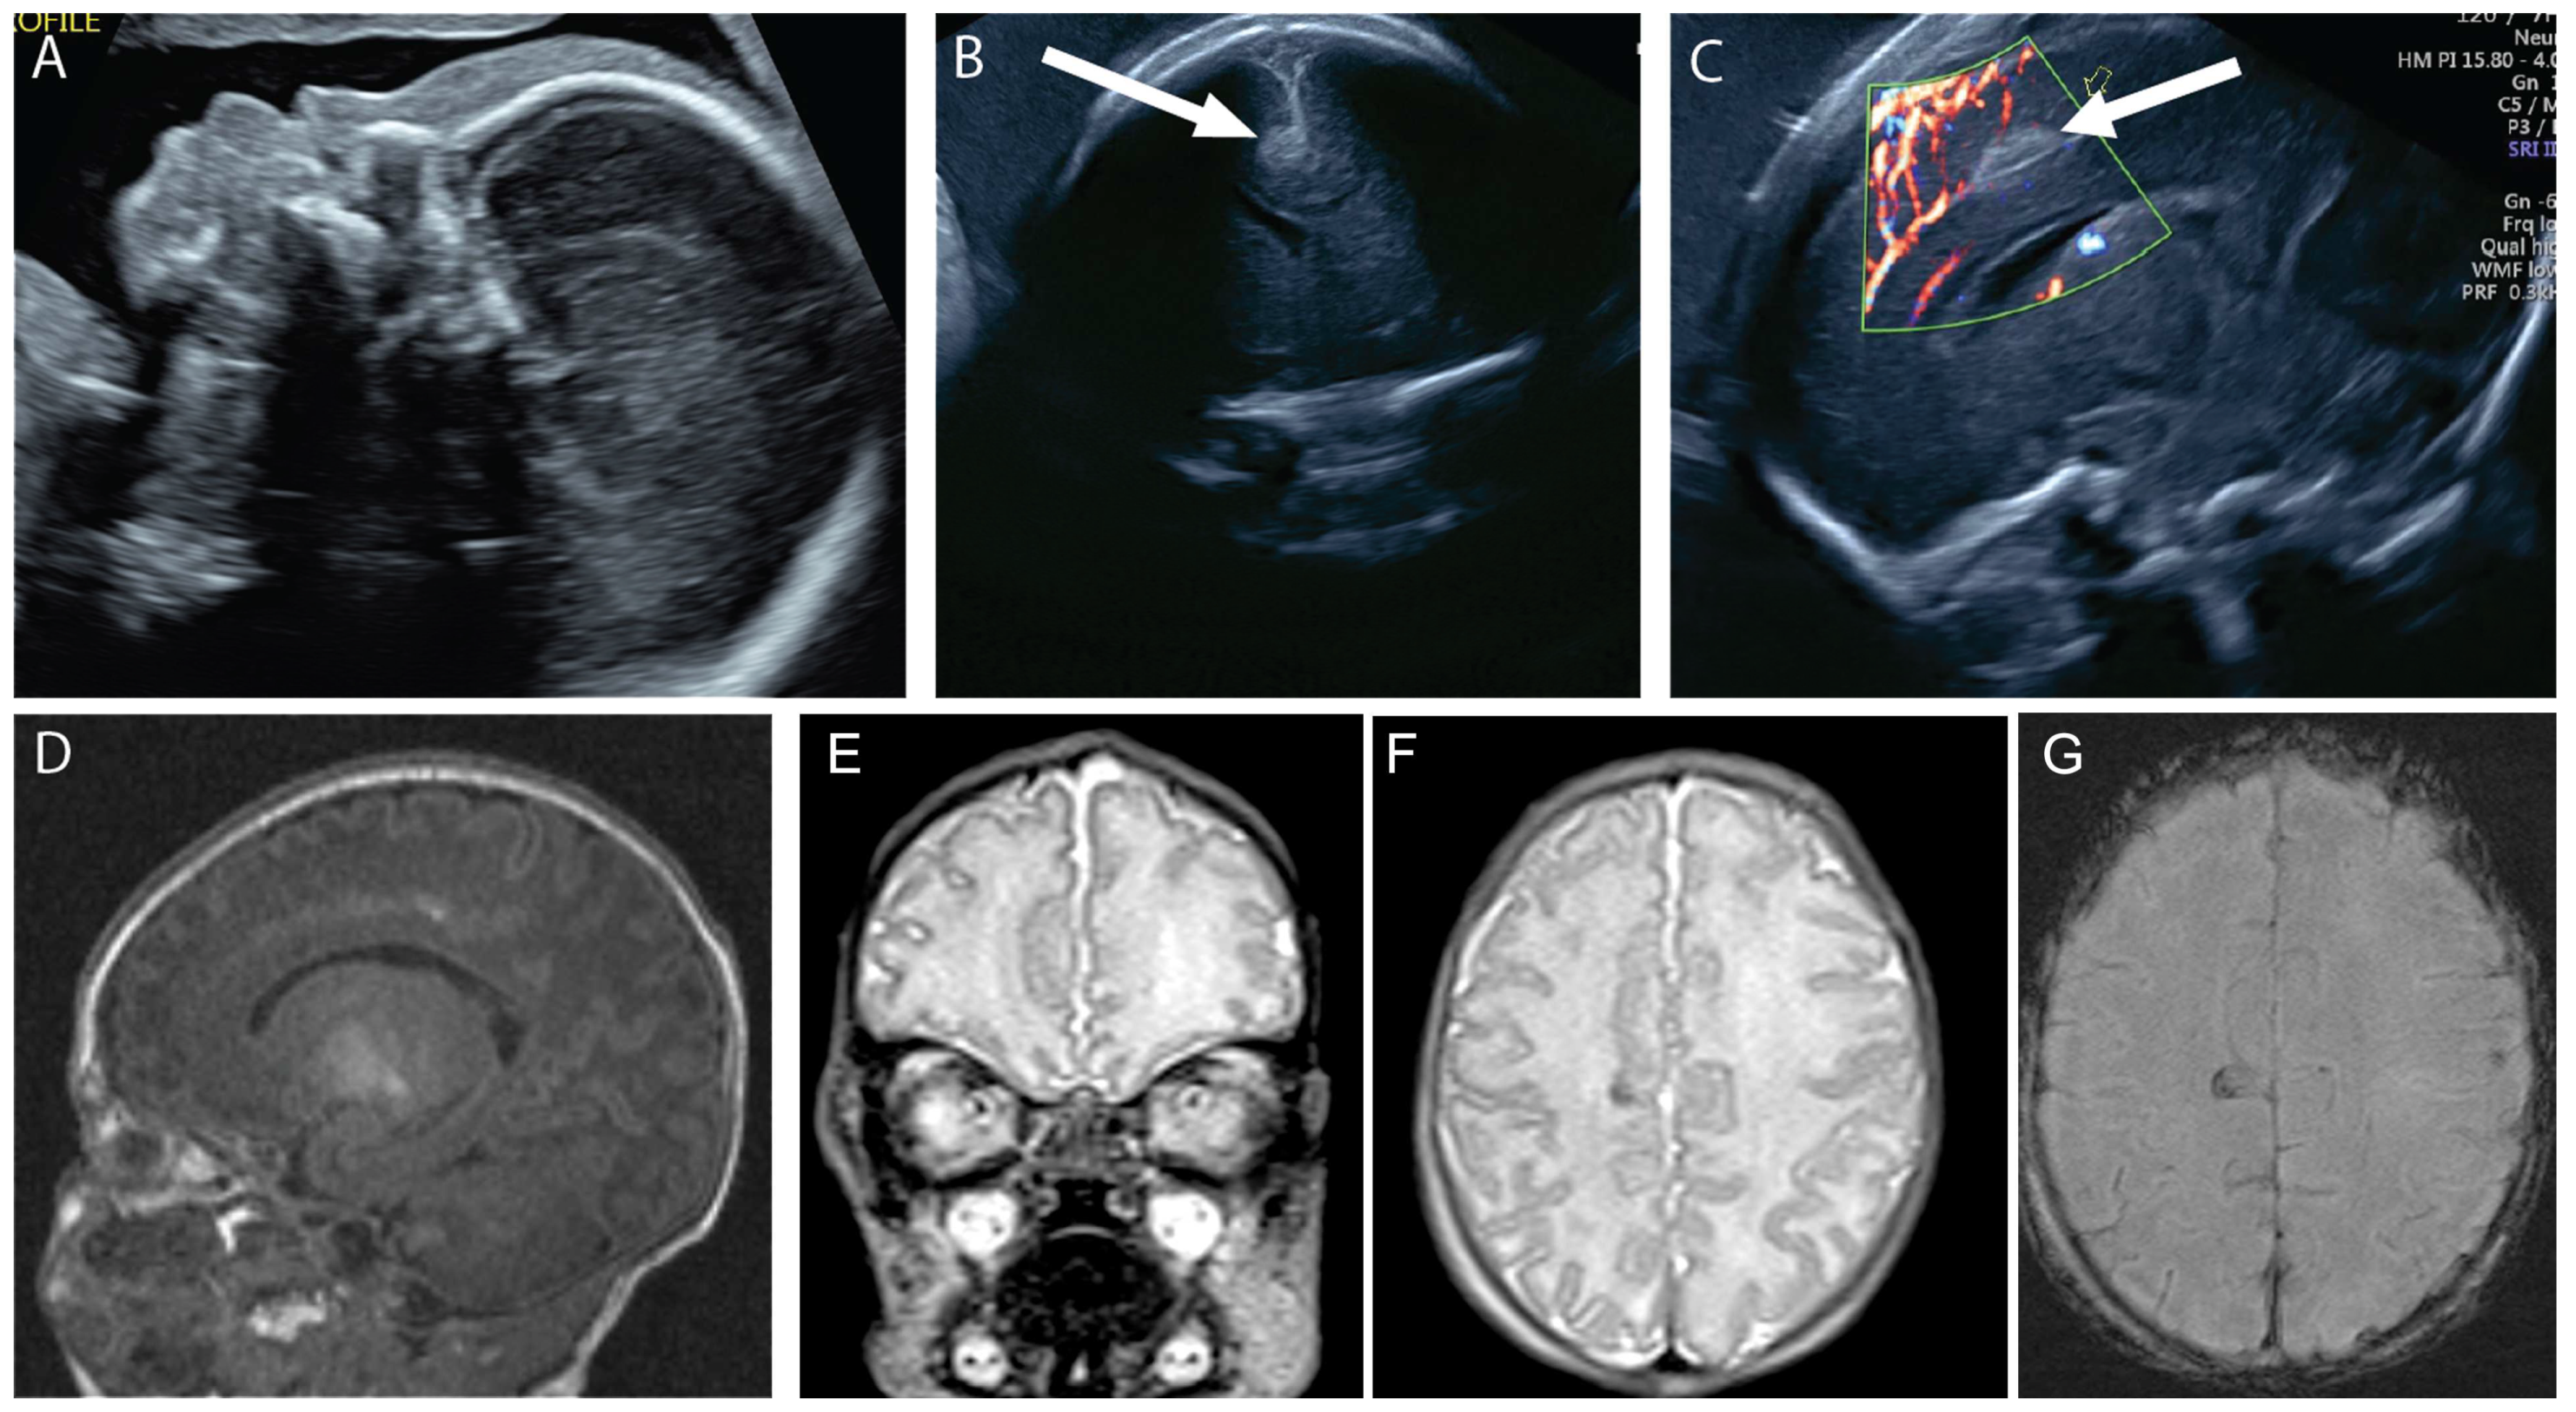

A 20-year-old G1P0 was referred for fetal midface hypoplasia (A). Neurosonogram at 25 weeks revealed a focal cortical abnormality in the right mesial cortex superior to the corpus callosum and just to the right of the falx (arrows, (B,C)). The patient’s cfDNA results were normal, and the mother declined amniocentesis. A fetal MRI at 26 weeks 2 days’ gestation revealed similar findings of mid-face hypoplasia and possible right medial cortical maldevelopment. Repeat MRI at 32 weeks’ gestation revealed similar findings (D). The baby was delivered vaginally at 37 weeks 2 days’ gestation and was admitted to the NICU. Postnatal MRI showed focal cortical abnormality in the mesial aspect of the right frontal lobe (E–G). The progression of the echogenic finding in the mesial cortical region is compatible with thrombosis of a superficial mesial cerebral vein, which is frequently associated with necrosis and gliosis of the adjacent cortical area, which can be seen in the T2 signal drop and the associated susceptibility artifact on susceptibility weighted imaging. The child’s SNP array was normal male. At one year of age, the child was undergoing physical and occupational therapy for a missed developmental milestone. By two years of age, the child was meeting milestones but had significant behavioral problems.